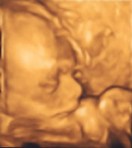

Joe and I are having a little boy. That is why I have been calling baby a he while he moves around–I’m glad I don’t have to change my pronoun. All was healthy and well with him. He was all curled up–I’m impressed with how flexible he is. We almost didn’t get any good pictures of him, but he peeked out his nice little head for one. He looks like he has Joe’s nose–but maybe not too. He’s also been kicking around for some time so that I could feel him–Joe even has a couple of times. It’s really fun right now.